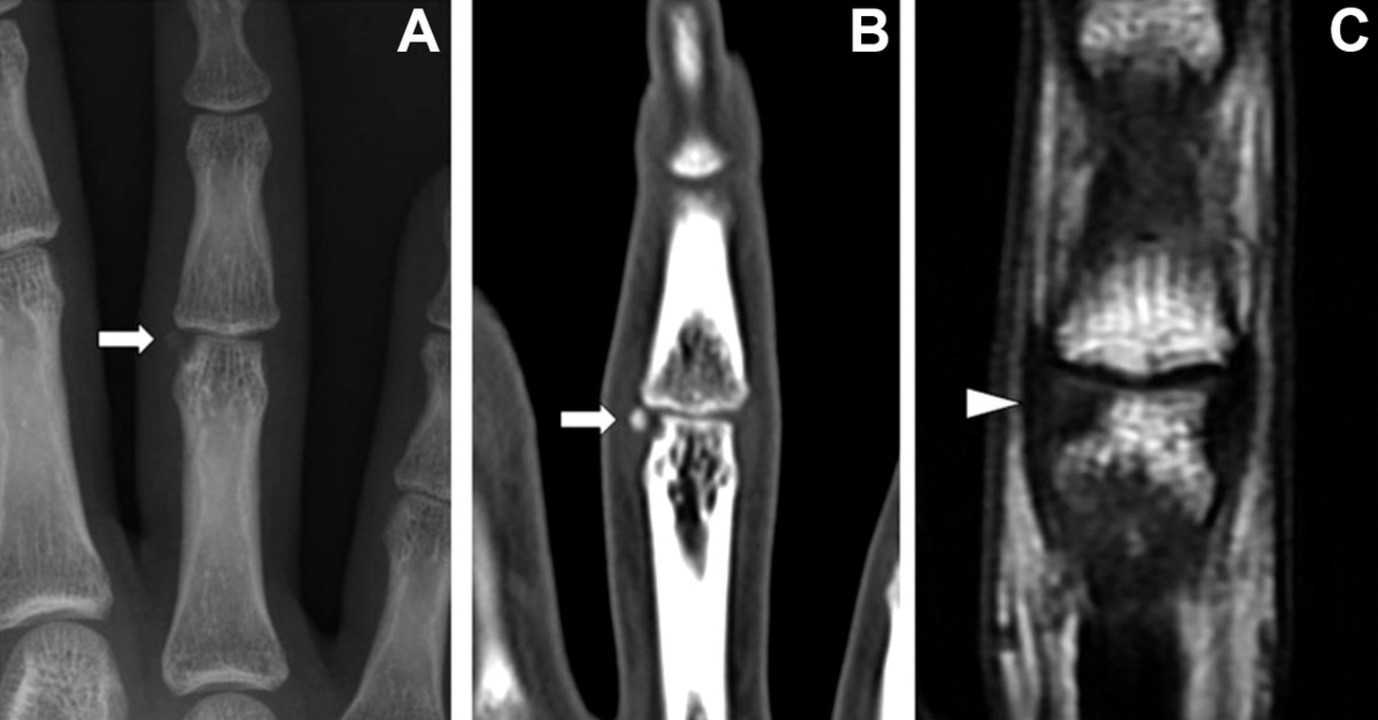

Сравнение рентгена, КT и МРТ безымянного пальца. Рентгеновский снимок (A), КТ (B) и МРТ (С). Фото: Case Reports in Plastic Surgery and Hand Surgery / ResearchGate (Creative Commons Attribution-NonCommercial 4.0 International license)